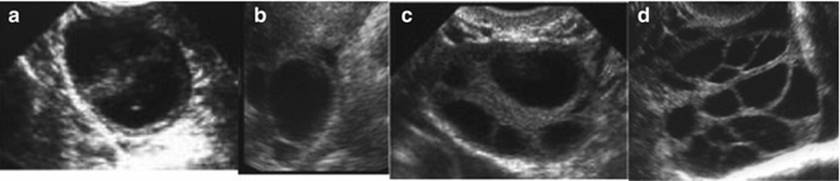

Monitoring Abnormal Response (Figs. 2.27, 2.28, and 2.29)

Fig. 2.27

Abnormal response to ovarian stimulation. (a) Premature luteinization, (b) LUF, (c) Poor response, (d) Hyper-response

Ultrasound is also useful in monitoring abnormal response to ovulation induction, which includes premature luteinization, LUF, endogenous LH surge, poor response, hyperstimulation, presence of retention or functional cysts, and ovarian torsion.

Premature Luteinization (Fig. 2.27a)

Follicles <15 mm with echoes are seen and these correlate with high P4 levels in the follicular phase. A premature and suboptimal LH surge results in progesterone production but no ovulation, and oocyte maturation without follicular rupture. It is associated with poor quality oocytes and embryos with an out of phase endometrium thus, reducing the implantation rate.

Luteinized Unruptured Follicle (LUF) (Fig. 2.27b)

Luteinized unruptured follicle is diagnosed when the dominant follicle is still apparent 48 h after administration of hCG or LH surge. The size of the follicle may reach 34–36 mm and has thick walls and may have internal echoes. The endometrium is thick and echogenic with no fluid in the pouch of Douglas. It is due to insufficient strength of the LH surge to induce follicular rupture but sufficient to induce oocyte maturation.

Endogenous LH Surge

Endogenous LH surge is seen on ultrasound as a premature rupture of follicles at a diameter of less than 16–17 mm. It is associated with compromised oocytes and embryo quality as a result of exposure to inappropriate LH levels. This requires extensive endocrine monitoring and can be prevented with the use of GnRH agonists or antagonists.

Poor Response (Fig. 2.27c)

Poor response can be predicted by estimating the baseline AFC and ovarian volume (<3–4 AFCs and volume <3 mL). At times, the AFC may be normal but the women may not respond to gonadotropins for various reasons, so the presence of less than two to three follicles on ultrasound on day 7 of ovulation induction with gonadotropins also suggests poor response.

Ovarian Hyperstimulation Syndrome (OHSS) (Figs. 2.27d and 2.28)

Ultrasound is essential for the prevention, diagnosis, and monitoring of OHSS. Judicial use of TVS for follicular monitoring while inducing ovulation with gonadotropins remains critical for the prevention of OHSS. TVS is also used to monitor the ovarian volume, keep record of number of follicles and corpus luteum and their size, diagnose ascites and pleural effusion when monitoring for the progress of OHSS. Ultrasound can also be used to guide paracentesis of the ascites or pleural effusion in cases, which develop severe respiratory distress to avoid trauma to ovaries or other abdominal structures.